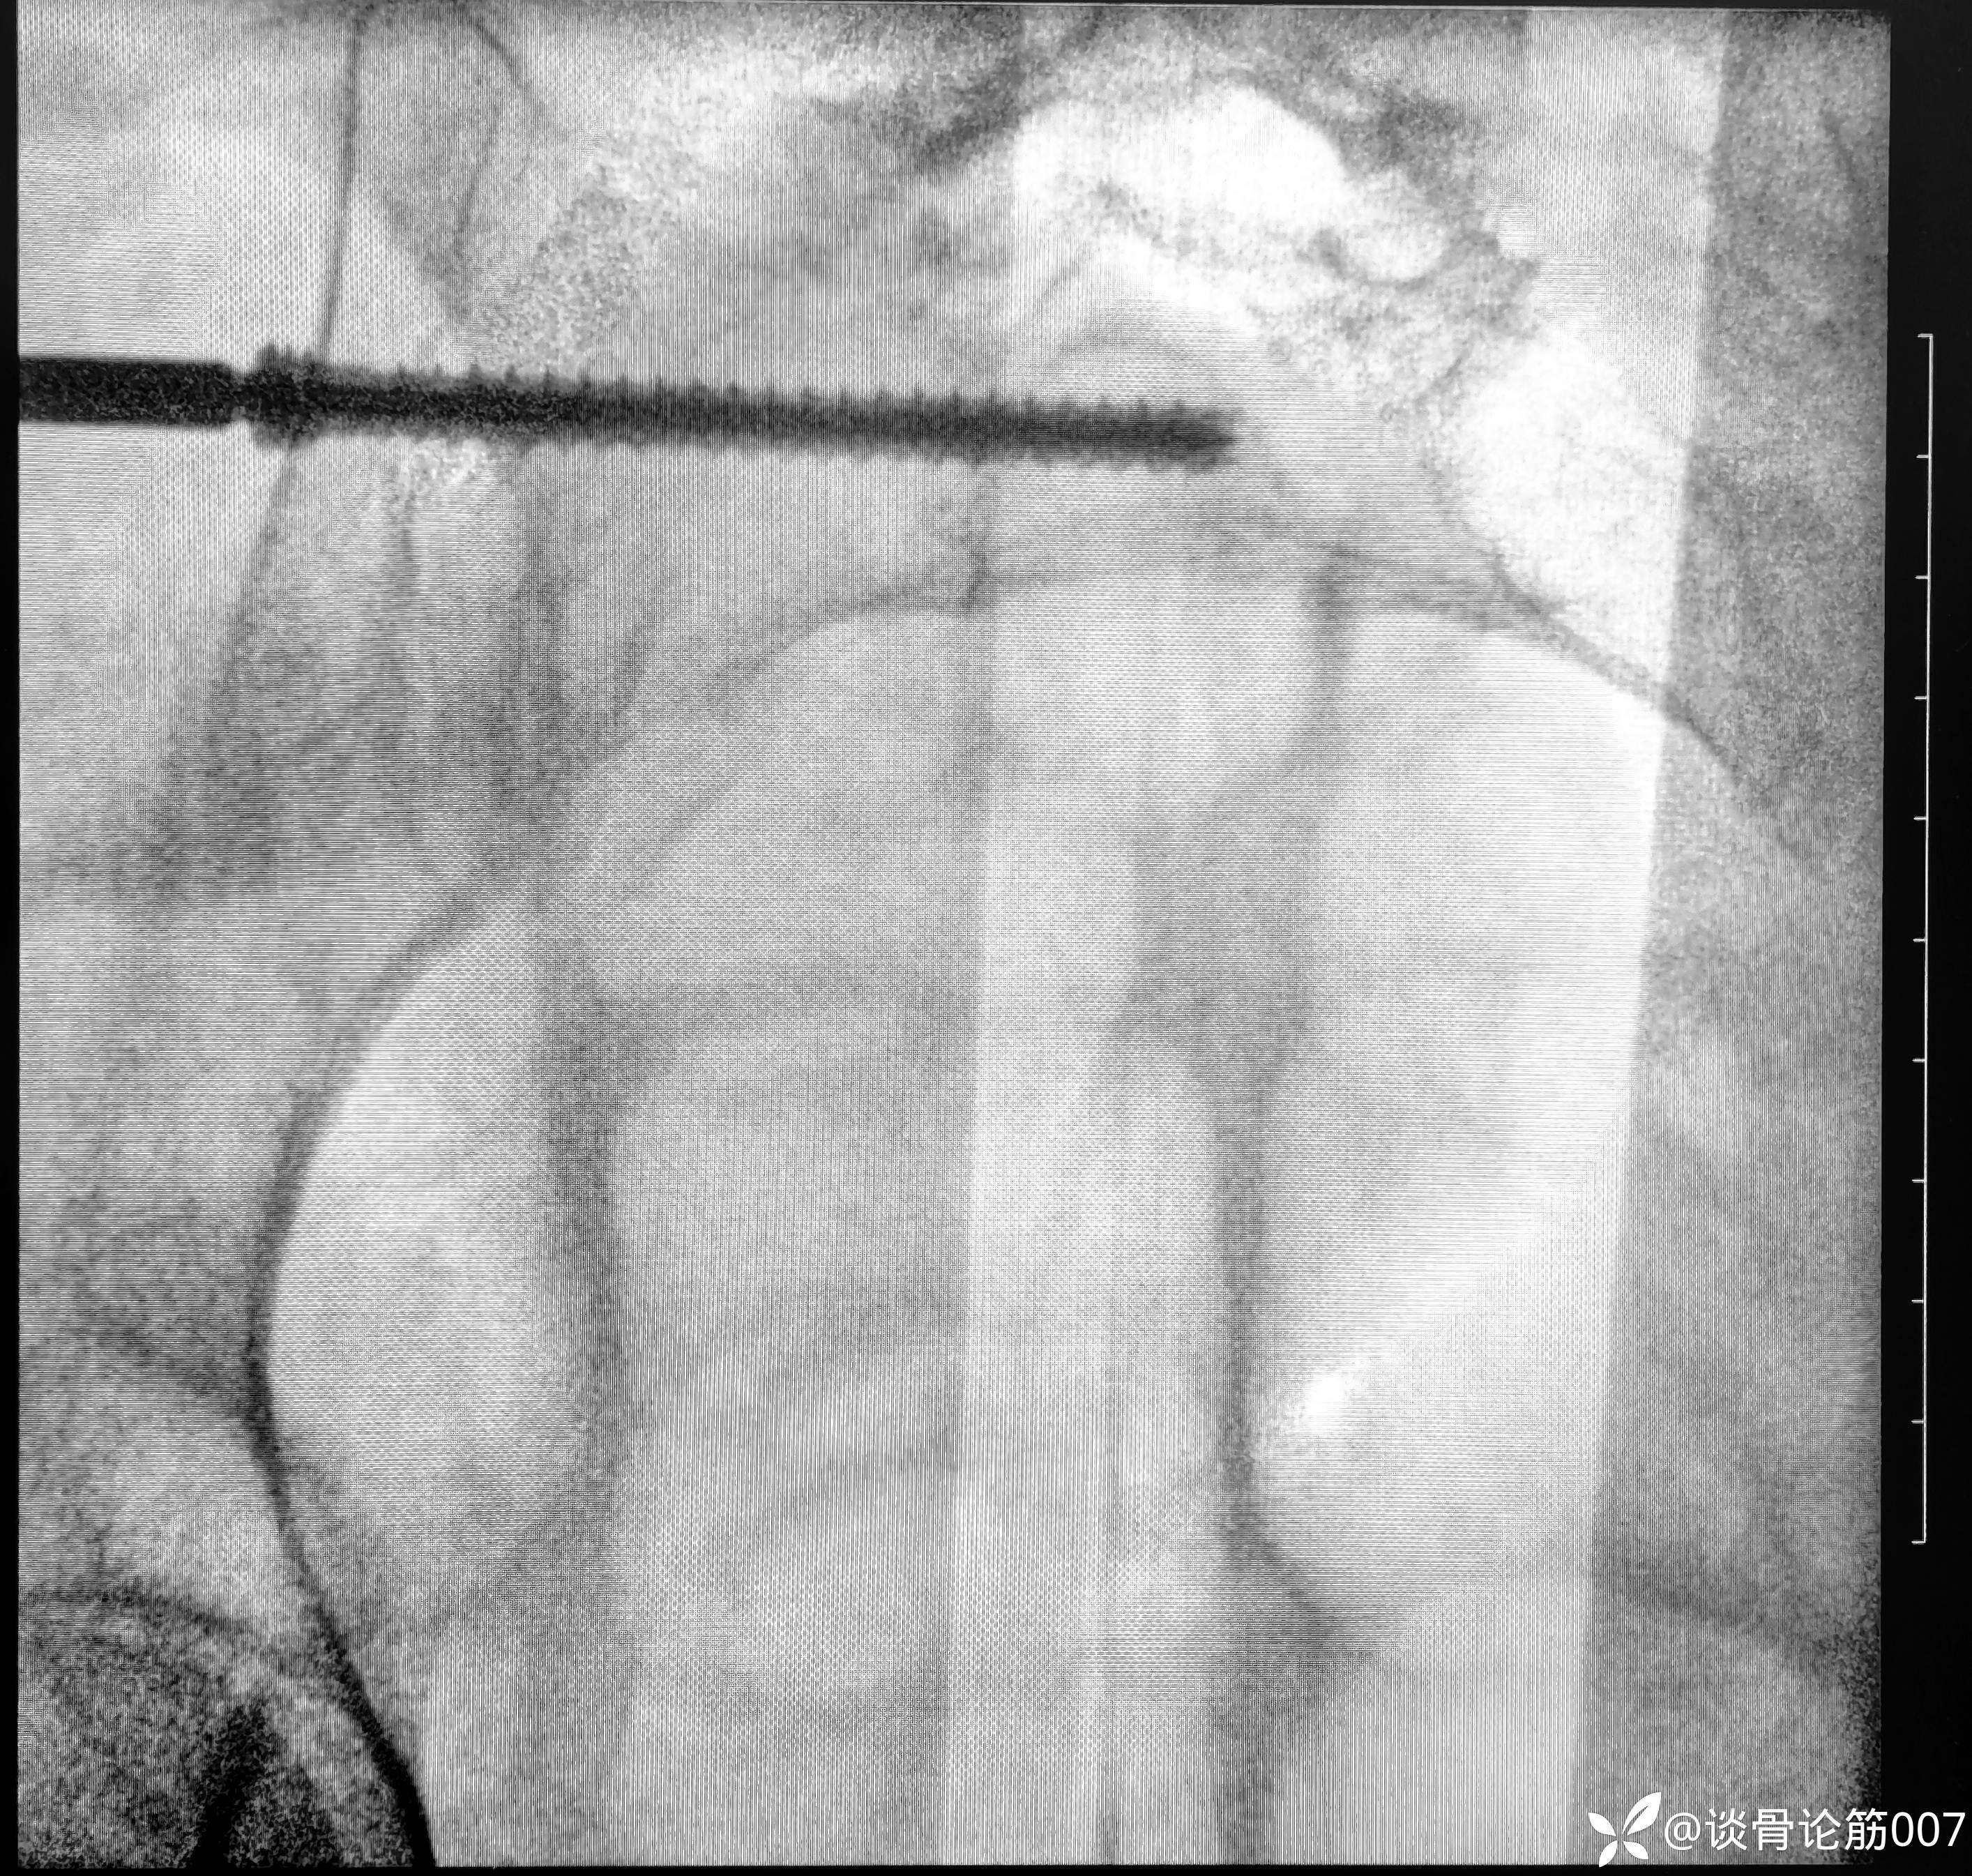

从结果来看,进针点应用粗钢针位置可能刚好一点

女性耻骨上支确实比较细

应用蛇钉技术避开髋臼